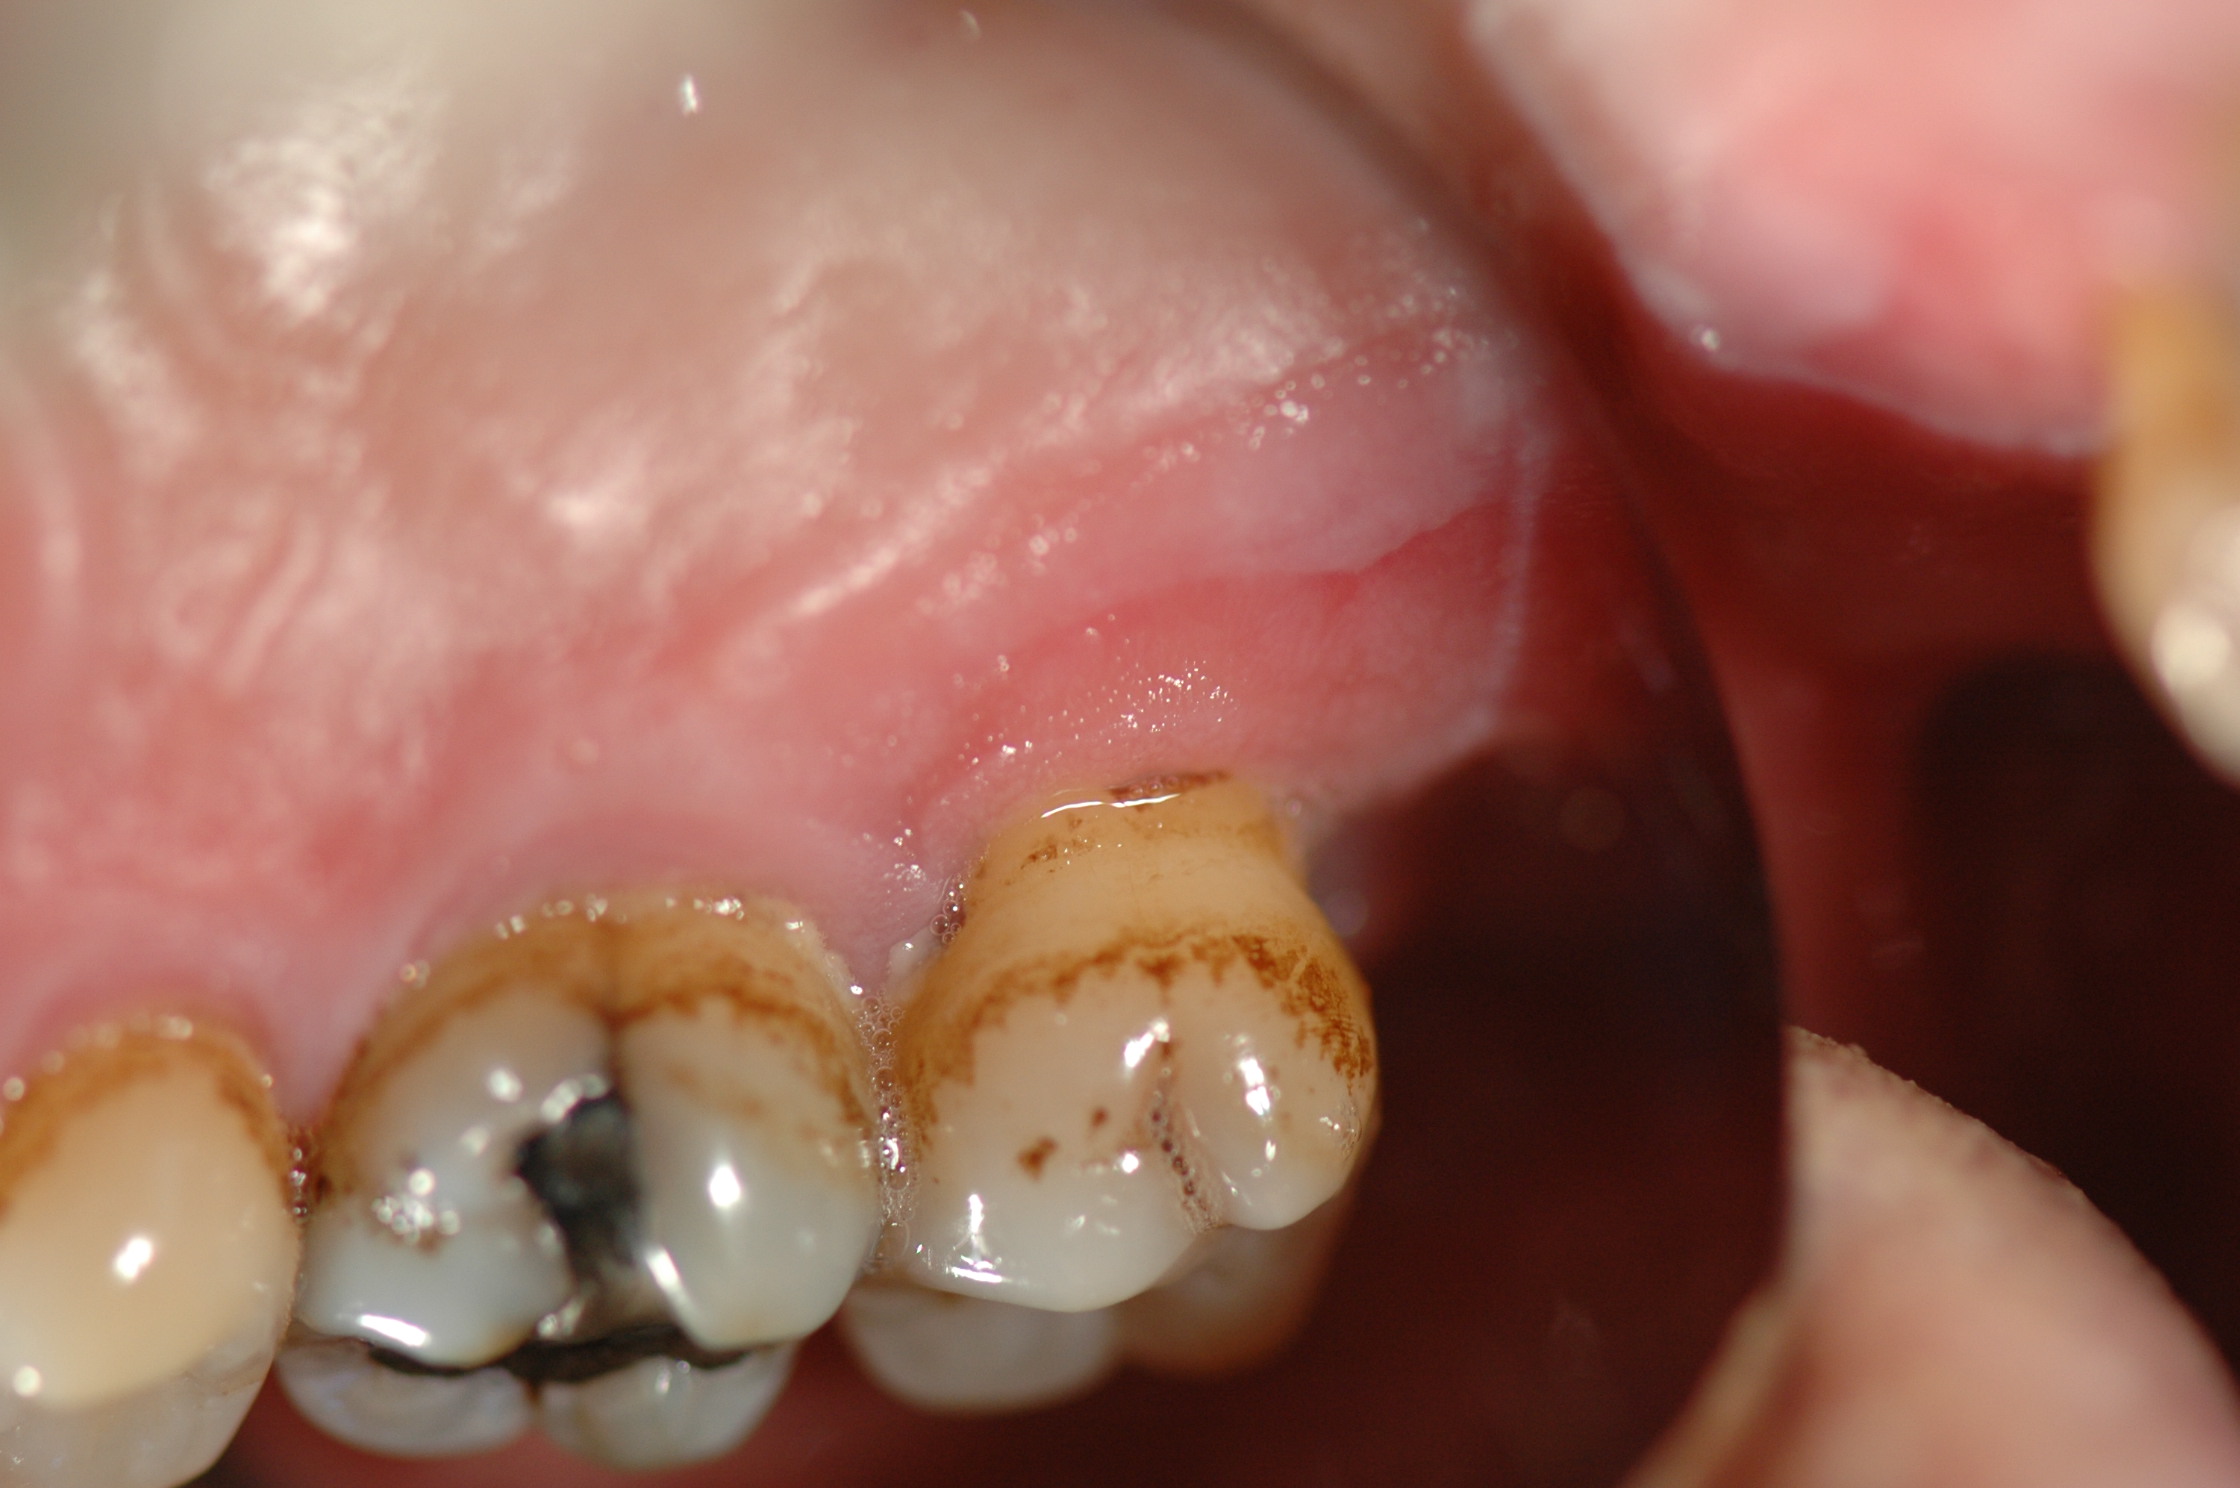

Publié le 05/09/2016Patient présentant des hyperplasies très volumineuses au palais, des deux côtés. Ces hyperplasies sont à l’origine de fausses poches.

En toute sécurité, une gingivectomie à biseau externe a été réalisée. Une gingivectomie à biseau interne aurait présenté des risques de section de la ou les artères palatines.